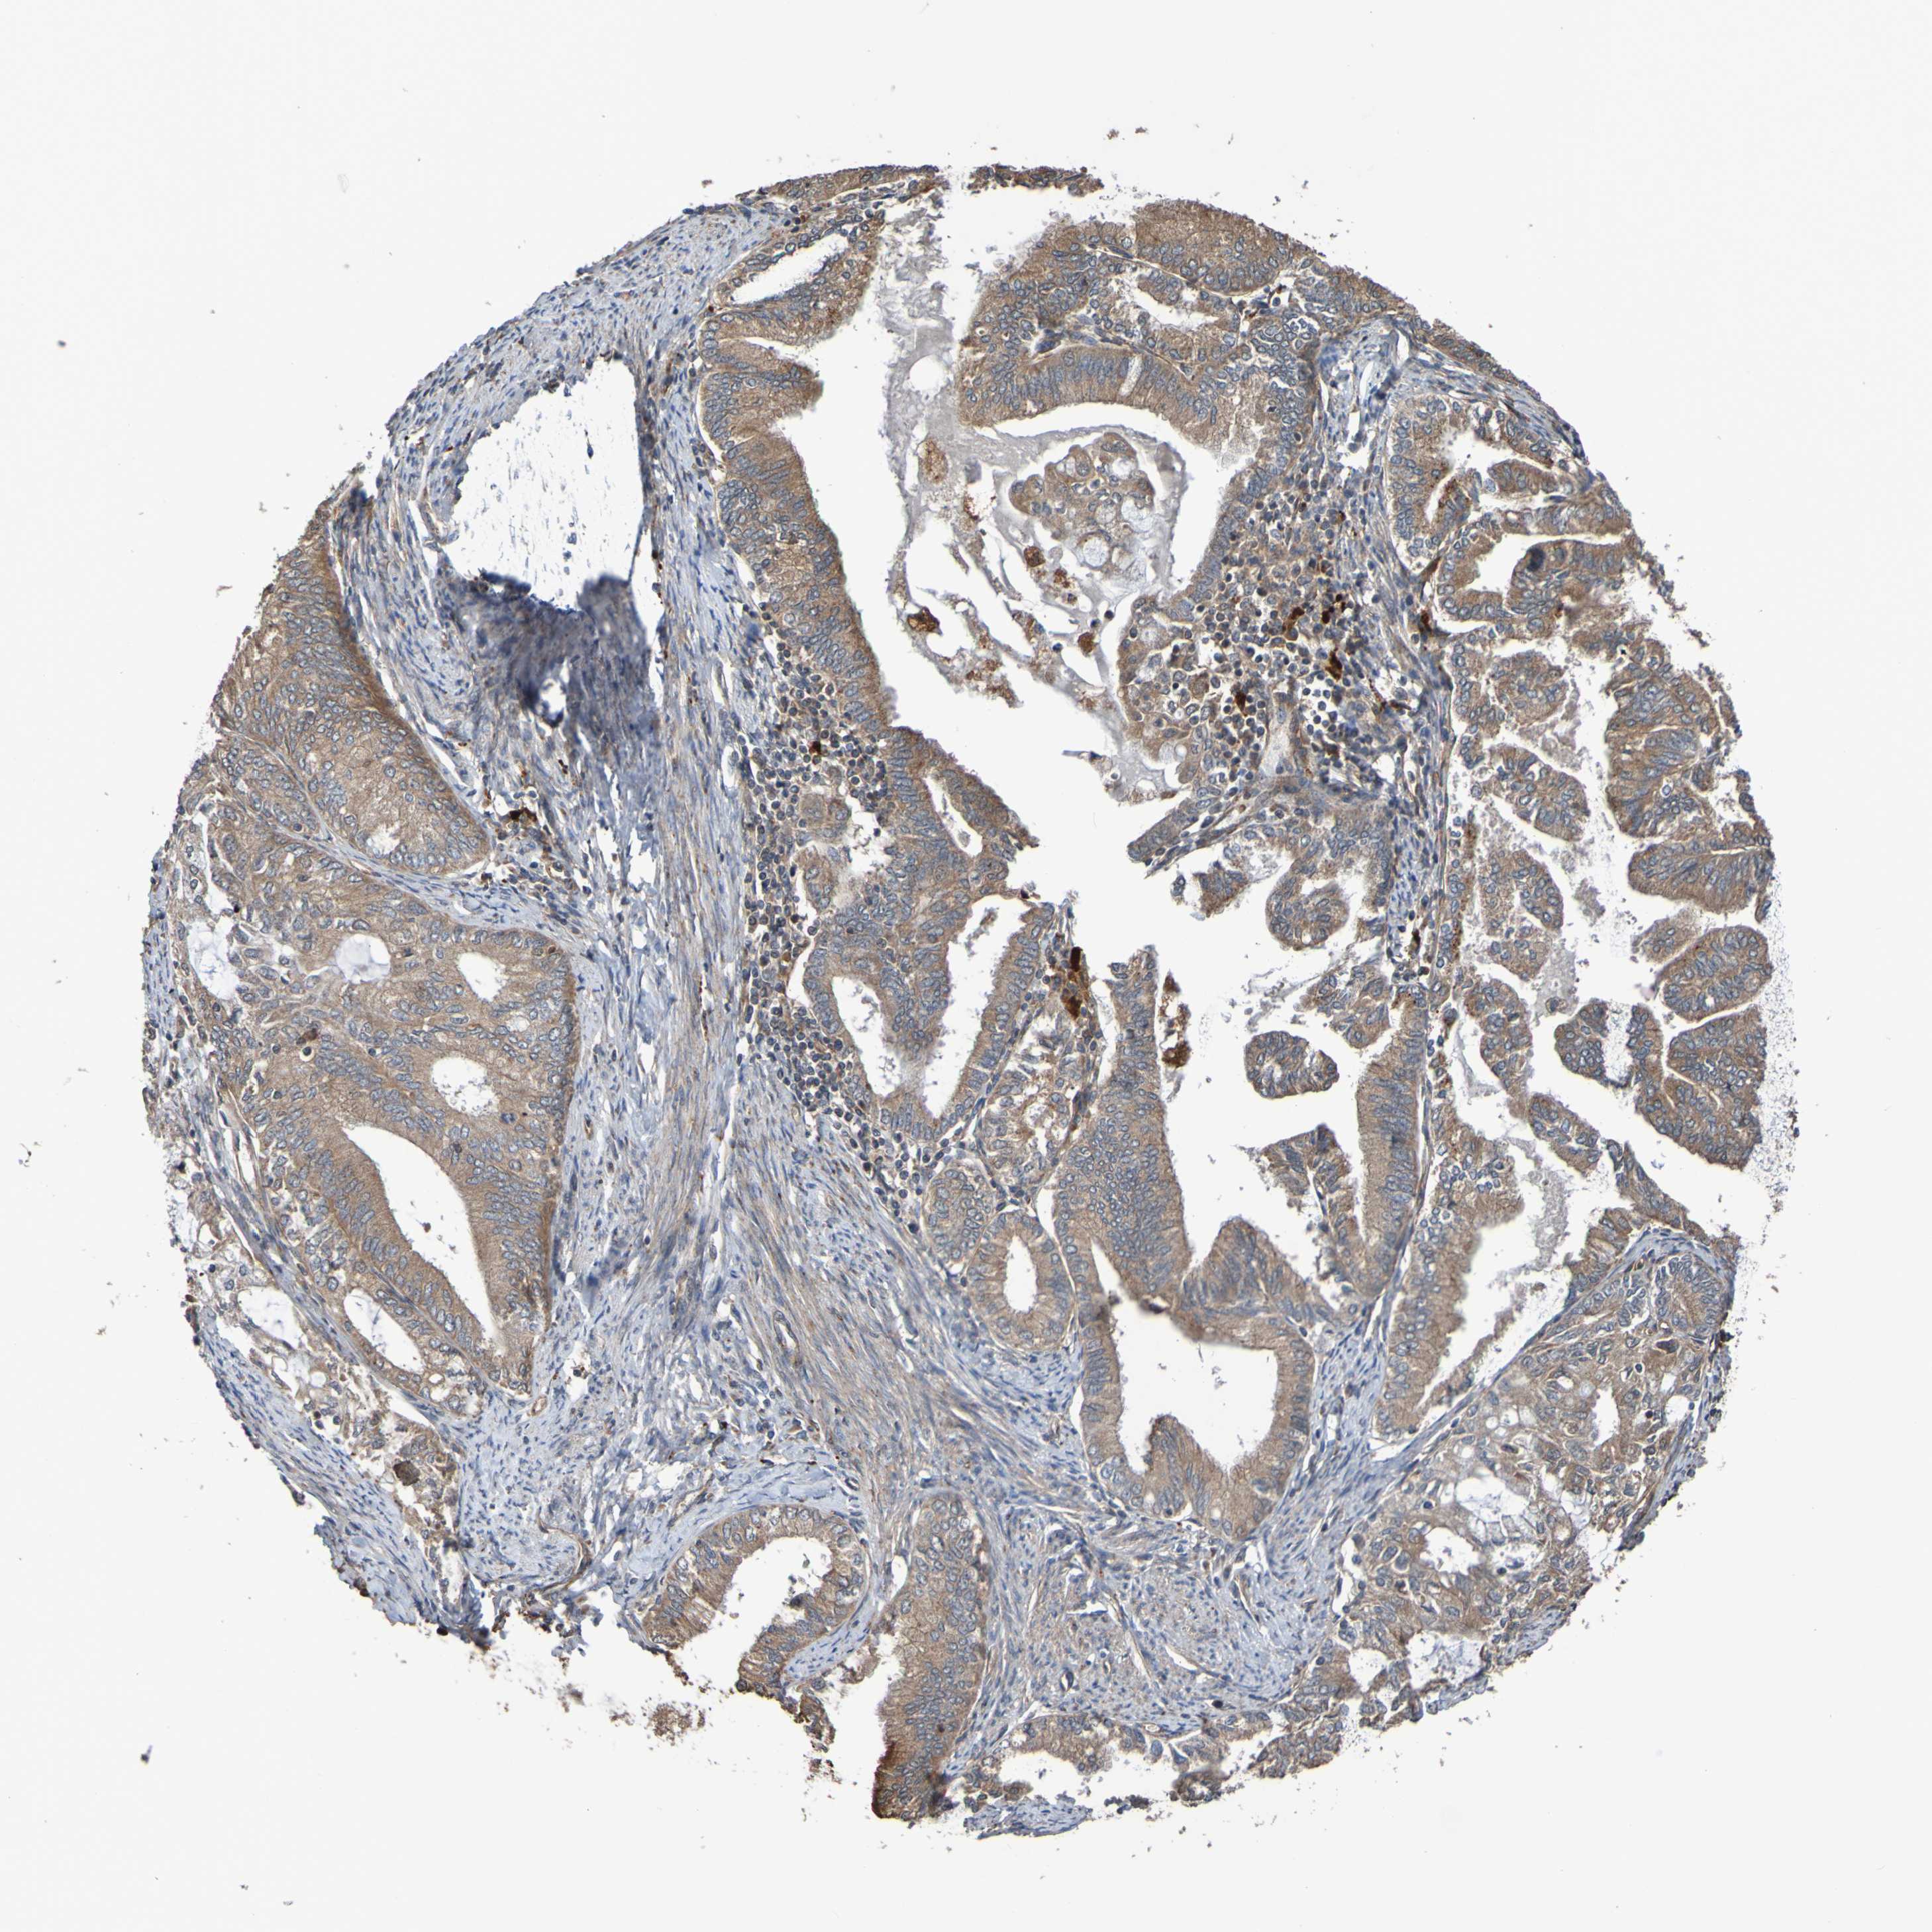

ENDOMETRIAL CANCER - Protein expressioni

A mouse-over function shows sample information and annotation data. Click on an image to view it in a full screen mode. Samples can be filtered based on level of antibody staining by selecting one or several of the following categories: high, medium, low and not detected. The assay and annotation is described here.

Note that samples used for immunohistochemistry by the Human Protein Atlas do not correspond to samples in the TCGA dataset.

Antibody stainingi

Antibody staining in the annotated cell types in the current human tissue is reported as not detected, low, medium, or high, based on conventional immunohistochemistry profiling in selected tissues. This score is based on the combination of the staining intensity and fraction of stained cells.

Each image is clickable and will lead to virtual microscopy that enables deeper exploration of all samples and also displays staining intensity scores, fraction scores and subcellular localization as well as patient and tissue information for each sample.

Antibody CAB010911

Staining

High

Medium

Low

Not detected

Intensity

Strong

Moderate

Weak

Negative

Quantity

>75%

75%-25%

<25%

None

Location

Nuclear

Cytoplasmic/membranous

Cytoplasmic/membranous,nuclear

Adenocarcinoma, NOS